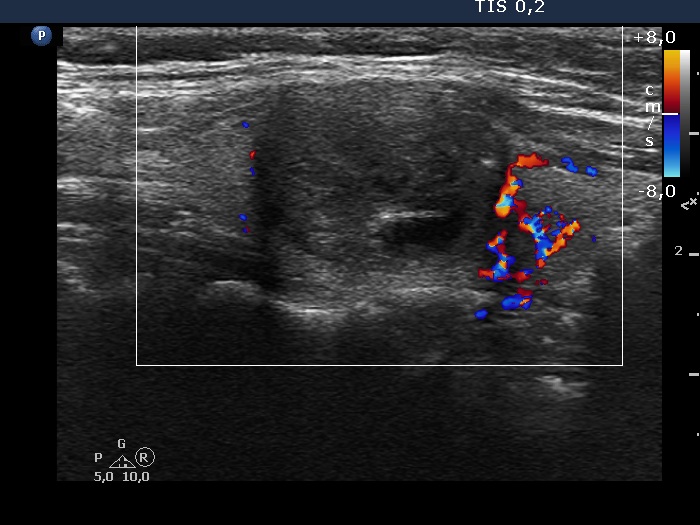

Right lobe, longitudinal scan

Right lobe, longitudinal scan, color Doppler mode. The nodule is avascular. The large vessel runs outside the lesion.